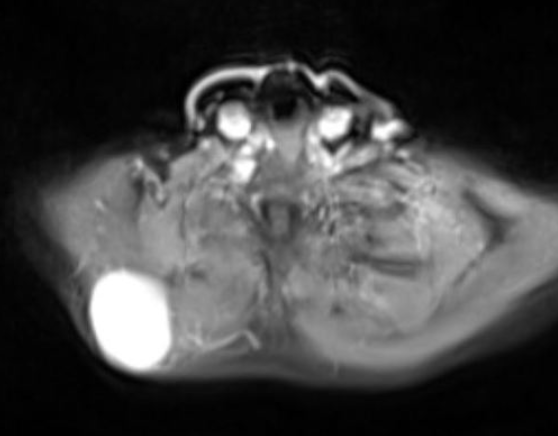

FIBROMATOSIS

Aneurysmal Bone Cyst